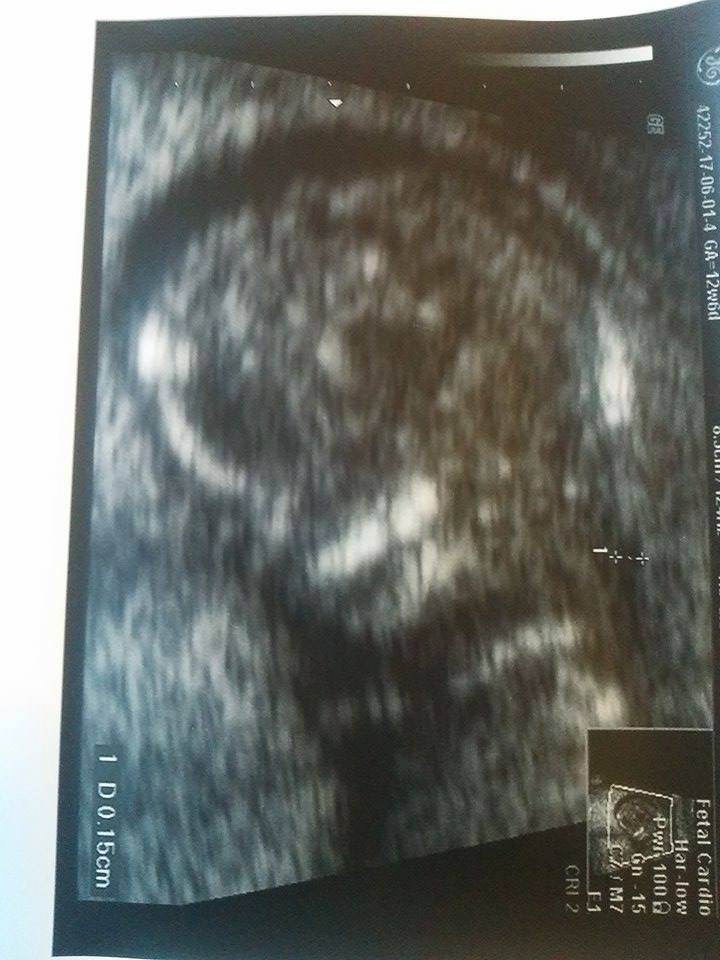

Gratki, kolejny chłopokNo to już jestem... maluszek zamiast 12t6d ma z usg 13t4d / 13t6d zależy od ujęcia do zdjęcia i jak to Pani dr stwierdziła jest ładnym 7.51 cm chłopcem z tętnem 164bpm.

W sumie płeć to było pierwsze co się dało u niego sprawdzić bo całe badanie się wiercił ale tak by prawie non stop mieć nogi rozłożone, aż się lekarka śmiała że wymachuje tym co ma... Nawet na początku powiedziała "nie mogę zbadać przezierności bo tak wysoko jest główka ale płeć widzę, chcecie państwo poznać?" bo miałam pierwotnie dopochwowe ale ze względu na wysokie ułożenie i tak się skończyło ganianiem go przez brzuch.

Poniżej przedstawiam Wam małego (z profilu i w całości, gdzie oczywiście też musiał się pochwalić płcią):